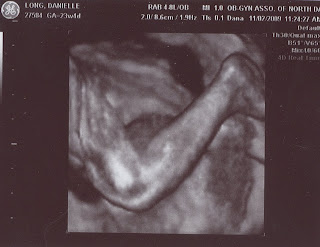

We had an appointment early last week and got to see his precious little face!

I had an egg and cheese omelet right before these pictures where taken so he was passed out. We kept trying to wake him up but he was too tired to show off for us.

What a stud-muffin?!?

Both Feet...our favorite picture!